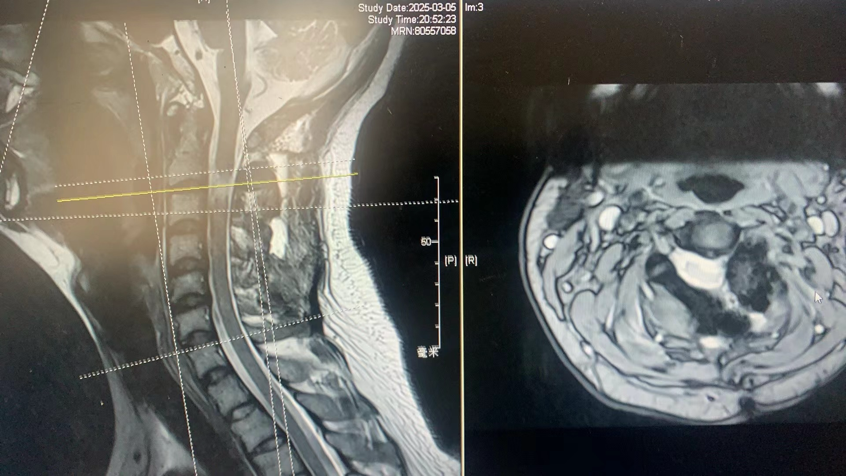

术后李先生的双腿力量迅速恢复,术后仅2天便顺利出院。无需引流管和导尿管,住院时间缩短了80%,康复速度远超传统手术方式。

手术后核磁共振证明肿瘤完全切除,脊髓恢复,没有脑脊液漏